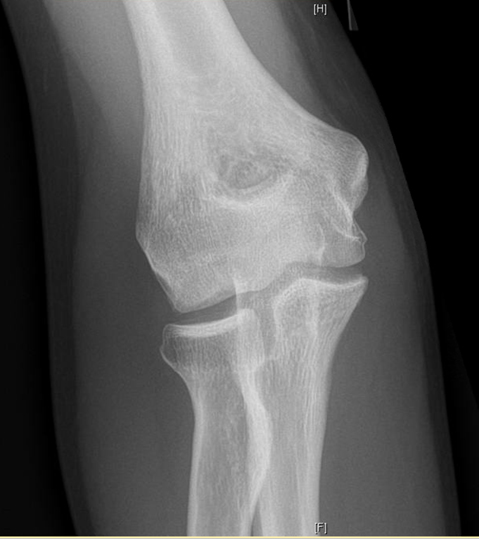

- Radiographs are used to detect the size, location and severity as well as skeletal age of the patient.

- Contralateral X-rays can help determine patients age as the affected side will have premature closure of the capitellum and radial head physes with delayed closure of the medial epicondyle and olecranon physes secondary to valgus stress overload

X-rays demonstrate a large lateral lesion within the capitellum consistent with an OCD lesion. The articular surface appears irregular